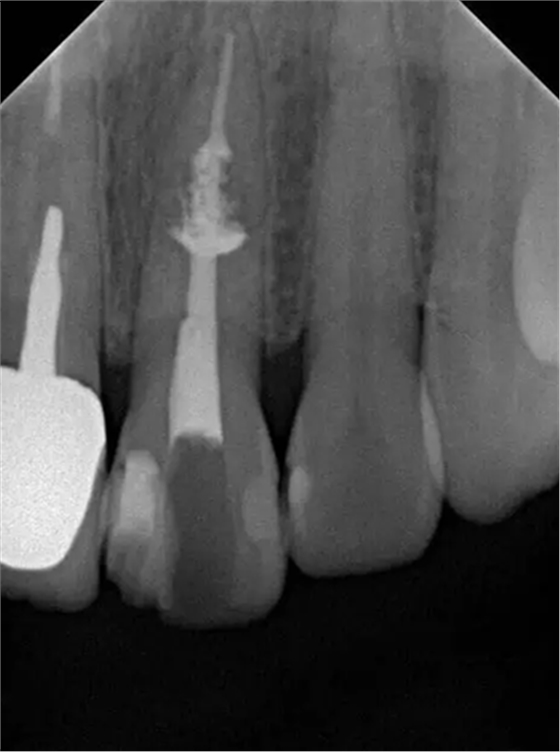

診斷:左上中切牙牙根內(nèi)吸收。治療計(jì)劃:左上中切牙根管治療,全冠修復(fù)。 治療過程:患者知情同意。使用含1/100,000腎上腺素的4%鹽酸阿替卡因(碧蘭麻,艾龍)局部浸潤麻醉,橡皮障隔濕。去腐未盡露髓,露髓孔出血多。開髓,使用10#不銹鋼K銼(MANI,日本)探查根管,根管中段有鈣化物阻擋,不能達(dá)到牙根全長(圖3A)。在顯微鏡下(Leica M400E,萊卡, 德國) 使用超聲尖(E1根管治療超聲尖,啄木鳥公司,中國)通開,采用根管長度測量儀(Root ZX, Morita公司,日本)加診斷絲片法(圖1B)測量根管長22 mm。使用控制扭矩馬達(dá)(X-smart,登士柏)和鎳鈦旋轉(zhuǎn)器械(Hero 642, Micromega)根管預(yù)備,根管預(yù)備過程中使用5.25%次氯酸鈉溶液沖洗。 根備完成后使用超聲蕩洗根管,5.25%次氯酸鈉溶液3 分鐘, 17% EDTA溶液1分鐘。干燥根管,使用螺旋充填器根管內(nèi)封氫氧化鈣糊,氧化鋅丁香油水門汀暫封。1周后患者復(fù)診,患者述無術(shù)后不適,檢查暫封完好,無叩痛,不松,牙齦無紅腫瘺管。使用橡皮障隔濕,去除暫封物,超聲蕩洗根管,5.25%次氯酸鈉溶液3 分鐘, 17% EDTA溶液1分鐘。干燥根管,牙膠尖(達(dá)雅鼎,中國)和必蘭根充糊劑(Cortisomol, 艾龍公司,法國)熱垂直加壓法根管充填。術(shù)后片顯示根充恰填,可見牙膠/糊劑被壓入鈣化物周圍和內(nèi)部縫隙內(nèi)